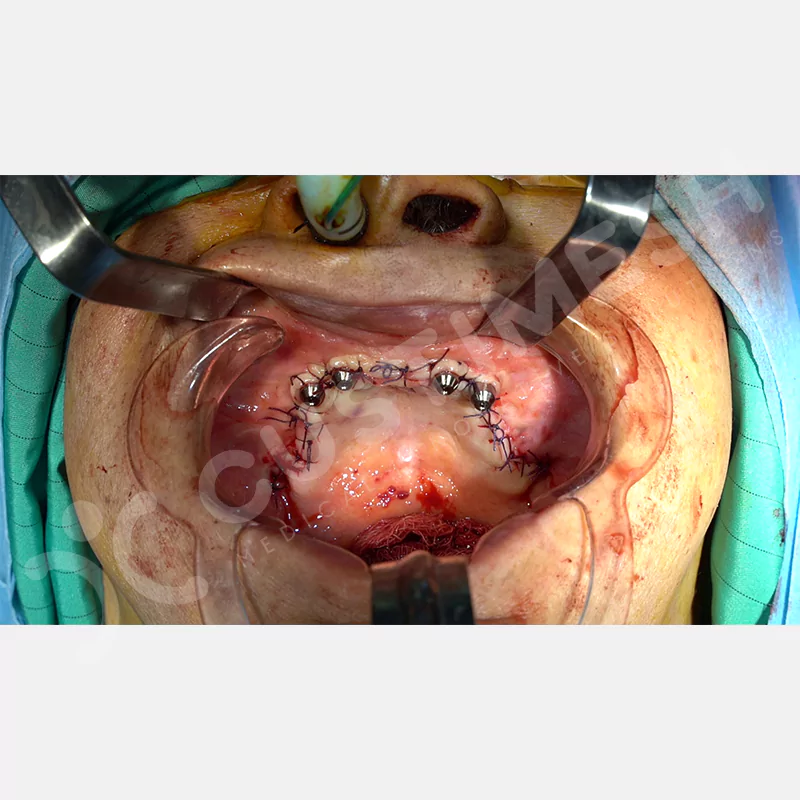

Modern diş hekimliğinde, çene gelişimini tamamlamamış veya ciddi kemik kaybı yaşayan hastalar için kişiye özel titanyum implantlar ile çözüm bulunmaktadır. CAD/CAM teknolojisi ve lazer sinterleme yöntemiyle üretilen bu implantlar, hastanın bireysel anatomik yapısına tam uyum sağlayarak geleneksel implantların uygulanamadığı vakalarda mükemmel bir alternatif oluşturmaktadır. Özellikle ileri derecede kemik kaybı olan hastalar için geliştirilen subperiosteal implantlar, periostun altına yerleştirilerek minimal invaziv bir yaklaşım sunarken, bilgisayarlı tomografi verileri ve sonlu eleman analizleriyle optimize edilmiş tasarımları sayesinde hem estetik hem de fonksiyonel sonuçlar garanti etmektedir. Bu yenilikçi teknoloji, tek seansta implant ve protez uygulamasına imkan vererek hastaların aynı gün doğal gülüşlerine kavuşmalarını sağlarken, kemik greftleme gibi ek işlem ihtiyacını ortadan kaldırarak cerrahi süreci büyük ölçüde kolaylaştırmaktadır. Kişiye özel tasarımı ve üstün biyouyumluluğu sayesinde, daha önce tedavisi mümkün görülmeyen kompleks vakalarda bile başarılı sonuçlar sunan bu implantlar, modern diş hekimliğinde yeni bir çağ açarak hastaların yaşam kalitesini artırmayı hedeflemektedir.

VAKA 1

VAKA 2

VAKA 3

VAKA 4